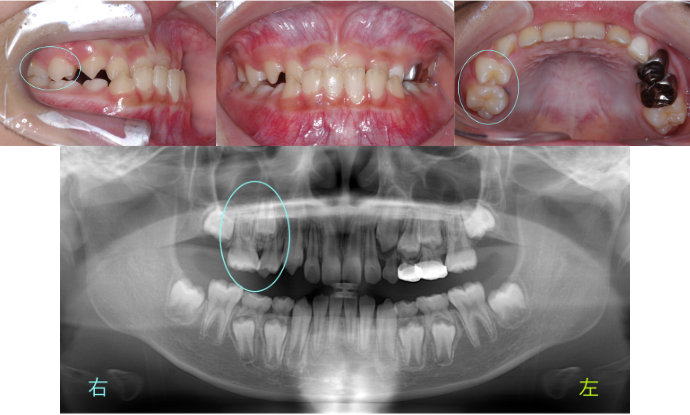

| Case11 |

| 受け口 および 右上の乳臼歯が早期に抜けたことにより、その後ろにある6歳臼歯が前方にずれている。そのため、6歳臼歯の直前にある永久歯が生える隙間がない。 |

| <治療前> |

|

| <治療後> |

| 主訴 |

前歯が反対になっている |

| 診断名 |

上顎右側第二乳臼歯の早期喪失による上顎右側第一大臼歯の近心転位、それに伴う上顎右側第二小臼歯の萌出スペース不足を伴う反対咬合

| 年齢 |

10歳 |

| 使用装置 |

マルチブラケット装置 |

| 抜歯部位 |

永久歯の抜歯は無し |

| 治療期間 |

3年8か月 |

| 治療費概算 |

検査・診断料:5万円+税 装置・技術料:25万円+税 来院ごとの処置・管理料:5,000円+税 保定装置料:5万円+税 |

| リスク・副作用 |

特になし |